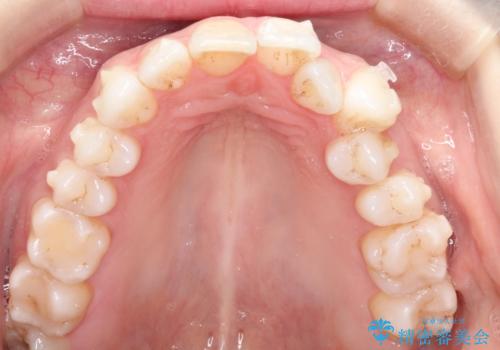

インビザラインによる非抜歯での八重歯の矯正

- 左上の八重歯と、上の歯のがたつきを主訴に来院されました。

上の奥歯を後方に移動させてスペースを作るのと、歯と歯の間をわずかに削り歯を並べる計画としました。

非常に強力的な患者様であったので、上下の正中も合わせ、ガタガタも改善することができました。